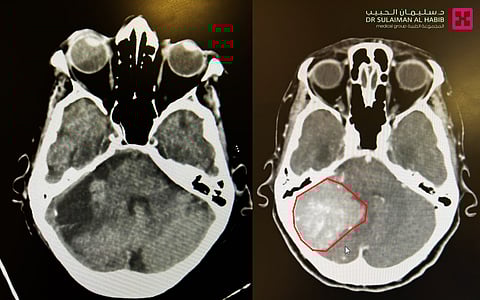

ذكر ذلك الدكتور وسام العيساوي استشاري جراحة المخ والأعصاب والعمود الفقري رئيس الفريق الطبي المعالج، والذي أضاف أن إجراءات الفحص السريري أبانت أن المريضة تعاني من مشاكل قلبية سابقة، تم على إثرها تركيب جهاز منظم لضربات القلب.. وبإجراء التصوير الطبقي المحوري (C.T Scan) أيضًا، اتضح وجود ورم كبير بحجم (4.5×4.8×4.3) سم ضاغط على المخيخ الأيمن؛ مما سبب لها حدوث استسقاء دماغي نتيجة الضغط على قنوات تسرب السائل النخاعي، وأدى إلى تضخم في البطينات.